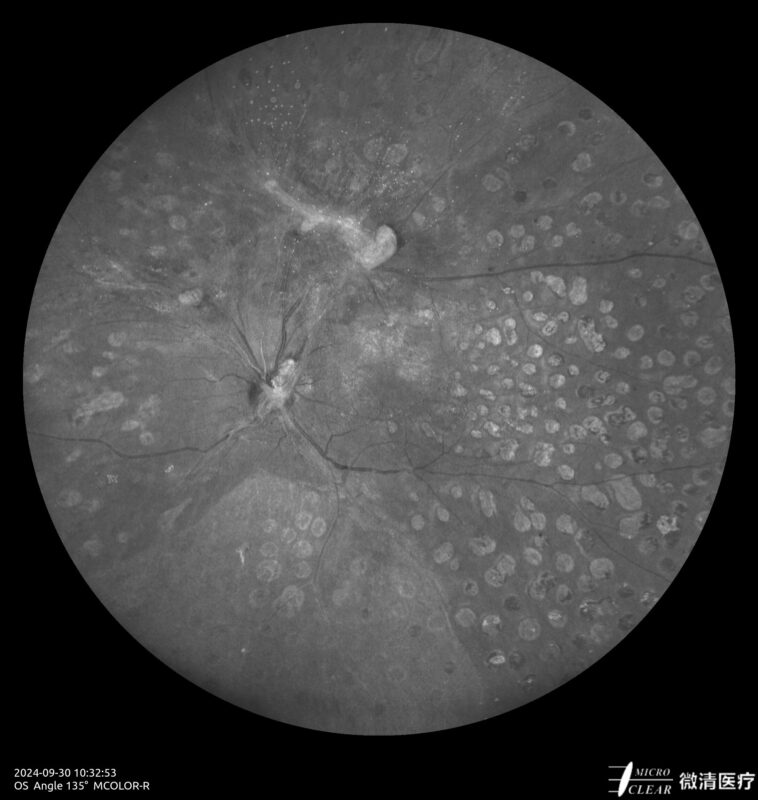

Ultra-groothoek en multimodale fundusangiografie gebaseerd op confocale scanning laser oftalmoscopie (CSLO).

- Multi-color imaging (MC): ‘Confocal SLO’ & ‘SLO based True Color’

- 135° WA (Groothoekangiografie) – in één opname